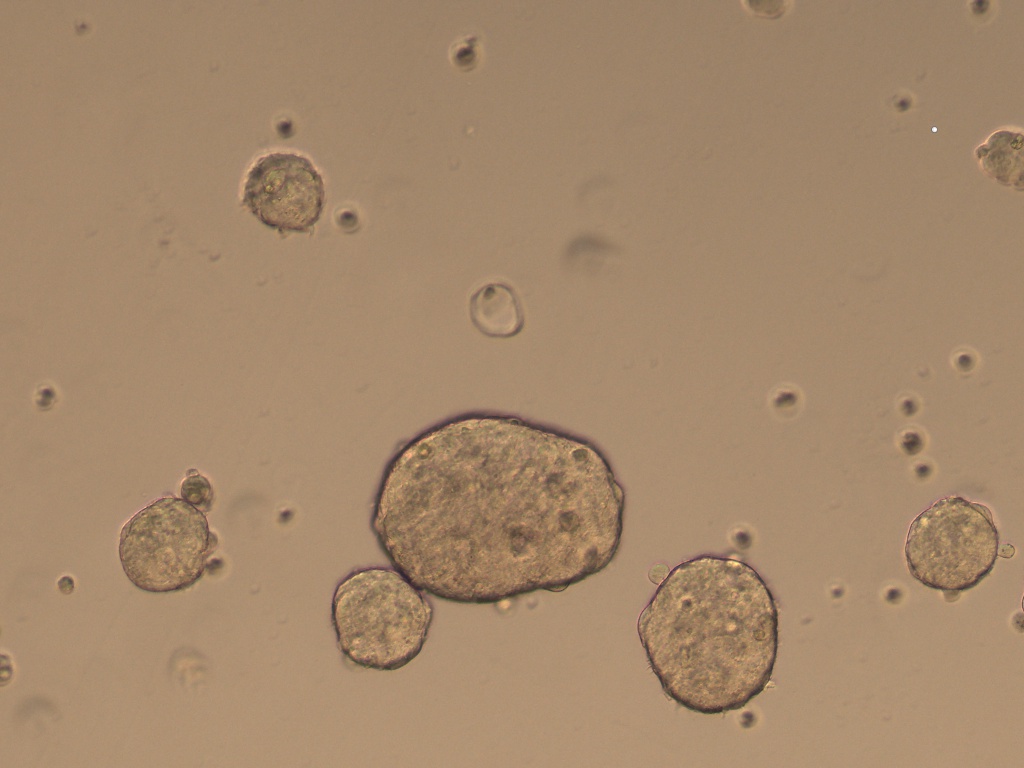

Cancer Stem cells Spheres Medium(肿瘤干细胞成球培养基)是一款用于将癌症干细胞(CSC)培养成3D球的培养基���。癌症干细胞(CSC)被定义为肿瘤内的一小部分细胞���,具有自我更新的能力����,并且经常在化学疗法治疗后驱动肿瘤的进展和复发����。因此����,针对CSC的特定疗法的开发有望改善癌症患者的生存和生活质量���,特别是对于患有转移性疾病的患者�����。

肿瘤干细胞成球培养基是一种新的化学成分确定和无血清的癌症干细胞培养基�����,可支持CSC形成3D球状细胞的聚集和扩增�����。

7、 4-10 天左右在超低吸附板孔中央区域会形成肿瘤球体;